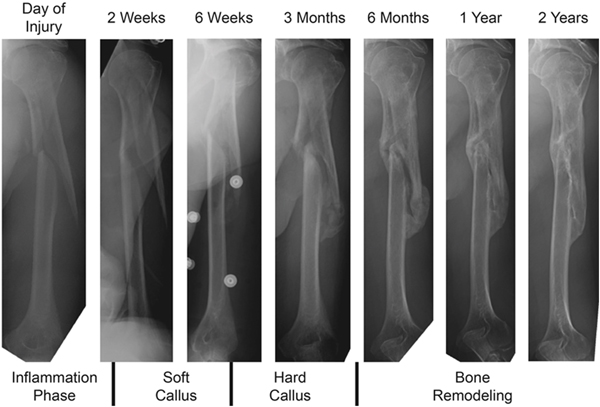

For most fractures, there are four phases to bone healing (Figure 1). First, inflammation that occurs within the first week, accompanied by fracture haematoma.14 The haematoma develops rapidly into a clot, which serves as a scaffold for new fibrous tissue and bone formation, and is accompanied by vasodilation, oedema formation and inflammatory mediator release.15 Second, soft callus that occurs within weeks 2–3, where granulation tissue is replaced by fibrous connective tissue and cartilage, causing fracture ends to become sticky.14 The most amount of healing happens around the capillary buds that invade the site of the fracture.15 Third, hard callus in weeks 4–12, where bone formation begins in the soft callus where strain is lowest.14 The callus is then ossified with the deposition of calcium hydroxyapatite crystals.15 Finally, remodelling, which can take weeks to years where woven bone is replaced with lamellar bone, especially where the load is greatest.14 This prolonged period is characterised by cycles of osteoclast activity and new bone formation.15 It is this fracture healing process that guides management.

Figure 1. Clinical example of humerus fracture healing. Reproduced from Ghiasi MS, Chen J, Vaziri A, Rodriguez EK, Nazarian A. Bone fracture healing in mechanobiological modeling: A review of principles and methods.

Figure 1. Clinical example of humerus fracture healing.

Reproduced from Ghiasi MS, Chen J, Vaziri A, Rodriguez EK, Nazarian A. Bone fracture healing in mechanobiological modeling: A review of principles and methods. Bone Rep 2017;6:87–100. doi: 10.1016/j.bonr.2017.03.002, with permission from Elsevier.42